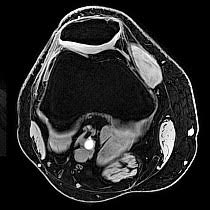

Our High-field MRI captures high-quality images. Our technicians who operate the scanner are certified in MRI and will stay in constant communication with you throughout your scan.

An MRI of the soft-tissue structures of the body—such as the heart, liver and many other organs - are more likely in some instances to identify and accurately characterize diseases than other imaging methods. This detail makes MRI an invaluable tool in early diagnosis and evaluation of many focal lesions and tumors.

MRI uses a powerful magnetic field, radio frequency pulses and a computer to produce detailed pictures of organs, soft tissues, bone and virtually all other internal body structures. The images can then be examined on a computer monitor, transmitted electronically, printed or copied to a CD. MRI does not use ionizing radiation (x-rays).

Detailed MR images allow physicians to evaluate various parts of the body and determine the presence of certain diseases. - How should I prepare for the procedure?